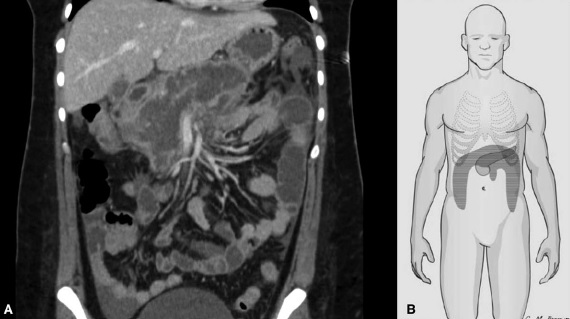

La nécrose pancréatique affecte les structures voisines, notamment les tissus mous péripancréatiques, le côlon et le mésocôlon (Fig. 1A) [11]. L’atteinte du mésocôlon peut compromettre le flux sanguin colique, entraînant une ischémie et des complications de l’ischémie, telles qu’une nécrose franche, une perforation et/ou une sténose ischémique.

L’extension directe de la nécrose pancréatique dans le côlon voisin (Fig. 1B) peut entraîner la formation d’une fistule ou d’un rétrécissement. La nécessité fréquente d’une antibiothérapie rend les patients atteints de NP susceptibles de développer une colite à Clostridium difficile [12].

Figure 1 : Image en coupe démontrant comment la nécrose pancréatique et péripancréatique entoure les structures intra-abdominales voisines (A). La nécrose péripancréatique peut s’étendre vers le bas, soit par la fuite pariétocolique, soit par la racine du mésentère de l’intestin grêle (B).